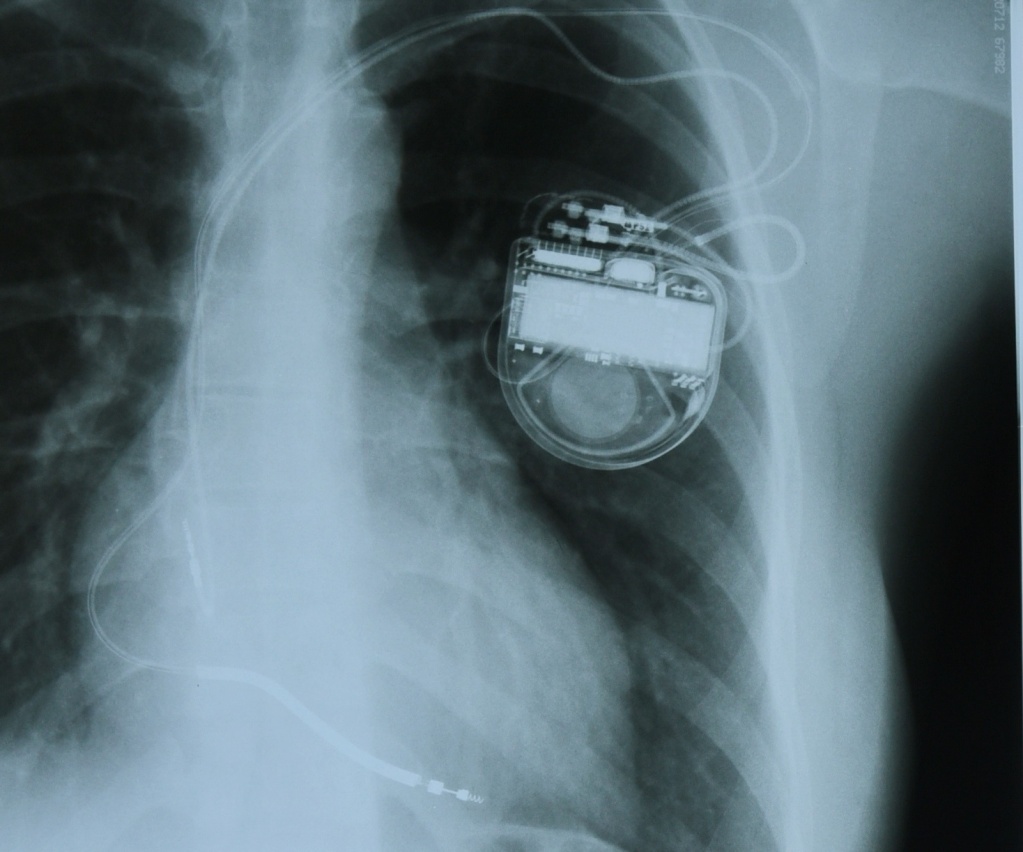

Устройство представляет собой небольшой, с ладошку, аппарат, состоящий из микросхемы и литиевой батарейки, который вшивают под большую грудную мышцу. Аппарат осуществляет считывание сердечных сокращений с помощью электродов, введенных в полость правого предсердия или правого желудочка, в зависимости от типа аритмии. То есть такая схема слежения за ритмом подобна обычной кардиограмме, но результаты этой записи фиксируются в микросхеме аппарата. В том случае, если ритм хороший, никакой электростимуляции не требуется. Если же у пациента произошел опасный для жизни приступ сердцебиения, кардиовертер улавливает эти нарушения и по электродам посылает сигнал небольшой мощности с целью синхронной деполяризации всех электрически активных клеток миокарда. Происходит электрическая «перезагрузка» миокарда, после чего должен восстановиться правильный ритм. Без кардиовертера сбой сердечного ритма может закончиться печально.

Операция проводится под местной анастезией. В подключичную вену вводится электрод кардиовертера. Под рентген-контролем его подводят к полости правого предсердия, а затем и в полость правого желудочка, «ввинчивают» электроды в их внутреннюю оболочку. А под кожу или под большую грудную мышцу подшивается сам аппарат. Когда рана затянется, а это произойдет на десятый день, он будет почти незаметен под кожей. Вся операция занимает не более часа и считается безболезненной для пациента. А на третий-четвертый день можно ехать домой и продолжать жить так, как хочется, не боясь проявлять самые разные эмоции. Ведь жизнь без эмоций, как небо без солнца, - неяркая и неинтересная.

Мы побывали на операции по имплантации кардиовертера рентгенохирургическим методом калужанке Яне, у которой с детства были проблемы с сердцем - врожденная желудочковая тахикардия мешала жить и радоваться жизни. А девушке всего 21 год, она закончила Калужский базовый медицинский колледж и собирается дальше продолжить обучение в институте, чтобы стать врачом-педиатром, лечить детей. Яна очень эмоциональная, подвижная, и сбои ее сердечко уже давало, что очень испугало девушку. Вот именно поэтому ей необходим кардиовертер, который в нужный момент придет на помощь, исправит сердечный сбой и спасет.